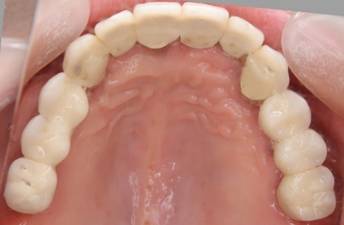

術後。上部構造はハイブリッドレジンです。しっかり嚙めるようになり喜んでいただきました。

下顎

上部構造装着後6年。ハイブリッドレジンを使用したため、少し艶がなくなってきました。上部構造の材料には金属、ハイブリッドレジン、セラミックなどがあります。セラミックはきれいですが欠けやすいため、最近はフルジルコニアを使っています。

下顎。12か月に一度メインテナンスをしています。